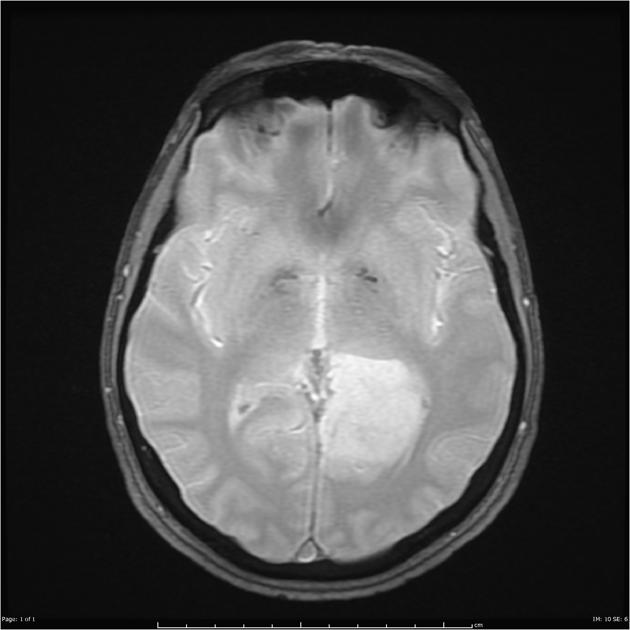

After a careful H&P with attention to neurologic symptoms, time of onset and rate of increase, imaging is critical to localization and diagnosis. Surgery, including a complete debulking if possible is the first line treatment, and sets the stage for the next step. Imaging is predominantly MRI based, with T1 ±gad, T2, FLAIR, diffusion weighted, and gradient echo sequences to identify and localize the extent of disease. Surgery is used to debulk the tumor completely if possible, and if not to obtain tissue for diagnosis.

Imaging

AA T1 without gadolinium

AA FLAIR

Radiotherapy General Fields

The treatment fields for HGG in pediatrics, similar to adults is the imaging enhanced region plus a margin. The initial GTV is the MRI T2 abnormality (edema). The initial CTV = GTV + 1.5 cm, corrected for anatomical barriers. The usual dose to this volume is 50.4 - 54 Gy at 1.8 Gy/fraction. The second GTV (boost GTV) is the T1+gadolinium enhancement. The second CTV=GTV+1 cm. This is then carried to 59.4 Gy.

• initial GTV = T2 or FLAIR mri image

• The CTV is the T2 GTV+1.5 cm margin, with corrections for anatomical barriers (⇒ 50-54 Gy)